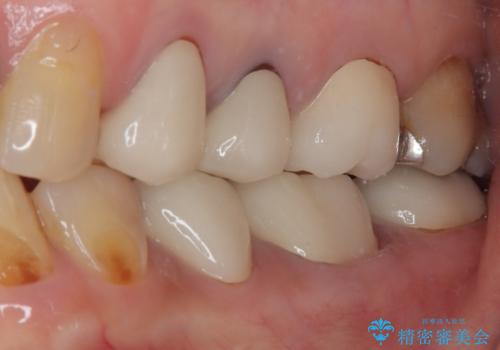

必要な歯に根管治療を行い、オールセラミッククラウンにて補綴治療を行うこととしました。

一部根管治療では症状が改善しなかったため、歯根端切除術を行いました。